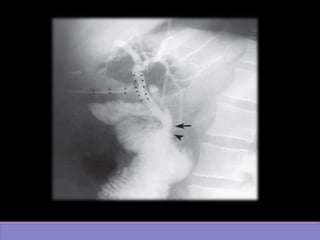

• #12 Colangiografia AP oblicua postoperatoria POSICION OPD (OBLICUA POST DERECHA Evidencia via biliar radiopaca por medio de contraste

• #13 Evidencia via biliar radiopaca por medio de contraste CON PRESENCIA DE TTUBO EN T CCOLEDOCO AMP DE VATER

• #14 Burbujas de gas (radio opaco) en conducto colédoco Estudio mediante fluoroscopia(POR ESO CONTRASTE NEGRO) evidencia imagen radioopaca de bordes definidos en conducto colédoco((burbujas de gas) Difernecia de pólipo y quiste en coleco clasificacion

• #15 Colangiografia postqx: AP oblicua muestra varias imágenes radiolucidas en via biliar a nivel de colédoco(flechas)